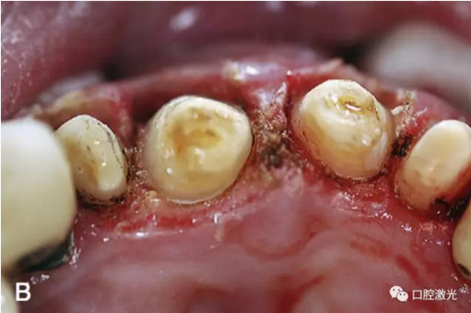

排齦是指使牙齦組織回縮,發(fā)生側(cè)向、垂直向位移,暴露出牙體預(yù)備完成線,創(chuàng)造一個(gè)清潔、干燥、無滲出的手術(shù)視野,以便制取印模。

口腔激光在固定修復(fù)中的應(yīng)用